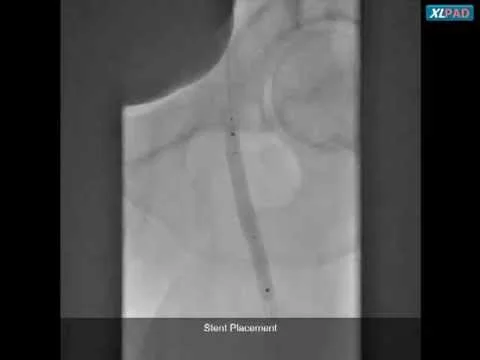

Big Boss Used for SFA CTO